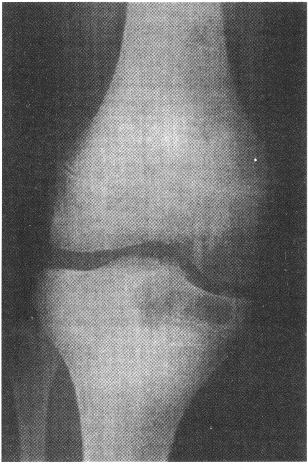

4.男,17歲。右膝關(guān)節(jié)疼痛1個月余,輕度腫脹。X線片示脛骨近端圓形骨質(zhì)破壞(如圖),應(yīng)考慮的診斷是

正確答案:C 解題思路:骨結(jié)核大多數(shù)繼發(fā)于肺結(jié)核。結(jié)核桿菌經(jīng)血行到達骨或關(guān)節(jié),停留于血管豐富的骨松質(zhì)內(nèi)而發(fā)病,病理上表現(xiàn)為滲出、變質(zhì)和增殖。